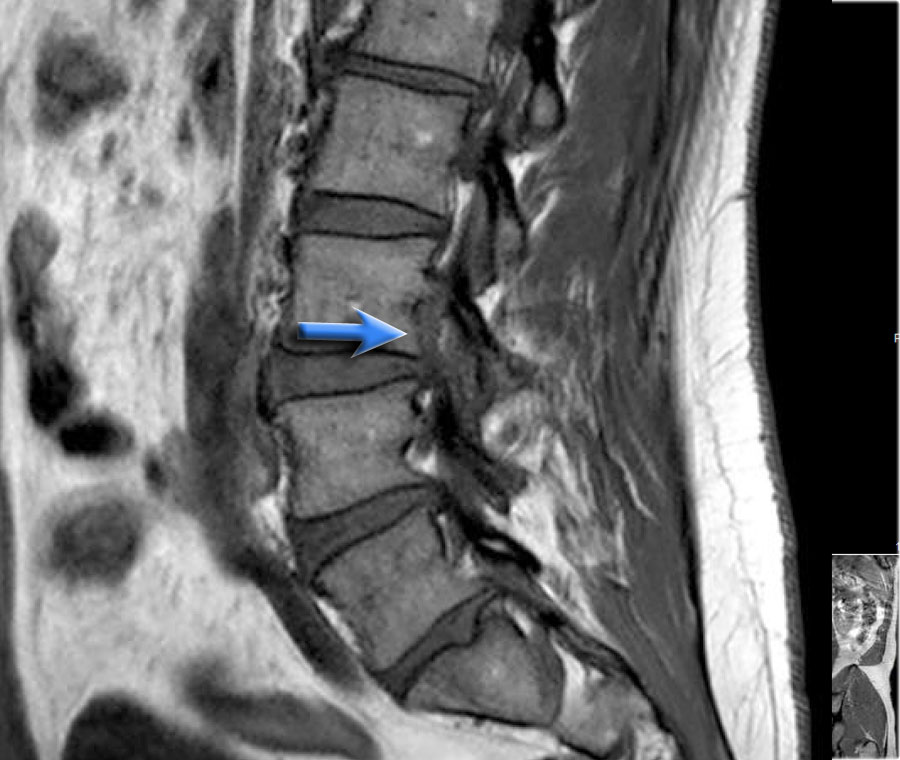

Hình ảnh lồi đĩa đệm khu trú tại mức L5S1.

Rễ thần kinh S1 bị chèn ép (mũi tên).

Hãy cuộn qua các hình ảnh và mô tả các dấu hiệu tìm thấy.

Sau đó tiếp tục đọc.

Các dấu hiệu tại các mức 1-4 như sau:

- Tại mức đĩa đệm, có hẹp ống sống tối thiểu do phình đĩa đệm và thoái hóa khớp mỏm khớp.

- Tại mức này, có hẹp ống sống nặng do phình đĩa đệm và thoái hóa khớp mỏm khớp.

Ngoài ra còn có rách vòng sợi (tăng tín hiệu) là nơi đĩa đệm thoát vị qua (mũi tên vàng). - Tại mức ngách bên, có thoát vị khu trú của chất đĩa đệm gây chèn ép rễ thần kinh L5 (mũi tên vàng).

Đây được gọi là thoát vị thực sự (extrusion), vì khoảng cách giữa các bờ của khối thoát vị lớn hơn khoảng cách tại nền. - Rễ thần kinh L5 bị chèn ép (mũi tên xanh dương) trong ngách bên.

Đĩa đệm thoát vị đã di trú xuống phía dưới và được thấy như một cấu trúc hình bầu dục nằm phía trước rễ thần kinh.

Đĩa đệm thoát vị không được bao bọc, tức là không được che phủ bởi các sợi của vòng sợi.